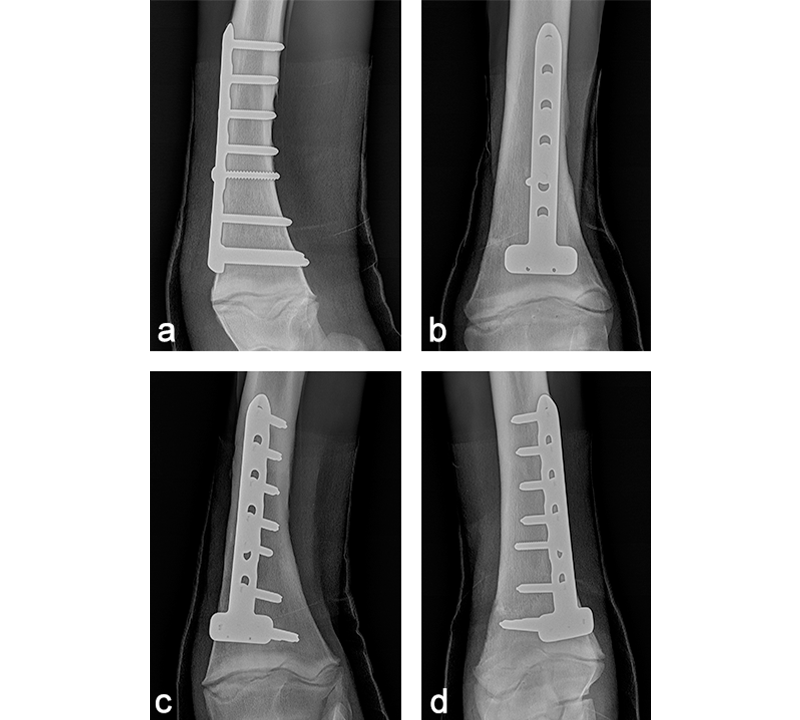

The foal was anesthetized and placed in dorsal recumbency. The left forelimb was placed in extension, clipped, prepared, and draped for aseptic surgery. A cranial approach to the distal aspect of the radius was made. The fracture was reduced, and a 6-hole LCP Equine T-Plate 4.5 was placed beneath the extensor carpi radialis (Fig 11). Two 5.0 mm locking screws were placed in the horizontal portion of the plate to engage the distal portion of the radius, just proximal of the distal radial physis. A 4.5 mm cortex screw was then placed into the second hole of the shaft of the plate, to provide interfragmentary compression and compress the plate to the proximal portion of the bone. The remaining holes were filled with 5.0 mm locking screws. The presurgical planning had included placing a second lateral LCP plate, however, the foals physiological status deteriorated. Further fracture fixation was therefore abandoned, and the surgery site was closed. A tube cast was placed from the level of the fetlock to the proximal radius. The foot and pastern were left free to minimize flexor tendon laxity. The foal was placed in sternal recumbency and required 2 hours of assisted ventilation before she started to breath spontaneously. Following surgery, she stood unassisted and was able to ambulate and suckle.

The cast was changed every 7 days and was replaced with a two-layer full limb bandage 28 days postoperatively. Carpal hyperextension was counteracted with an elastic band taped to the palmar aspect of the limb under tension, to prevent hyperextension when the limb was loaded (Fig 12). Tensions were adjusted depending on the increasing weight and strength of the foal. Once the cast was removed, the foal was hand walked daily.

Postoperatively, the foal was noted to have a moderate carpus valgus deformity. Radiographic assessment, however, showed that the lateral deviation was not due to malalignment of the fracture. A gradual improvement in the degree of valgus deformity has been seen with growth as the foal has matured (Fig 13). Radiographic healing of the fracture has proceeded quickly with very little callus formation (Fig 14).